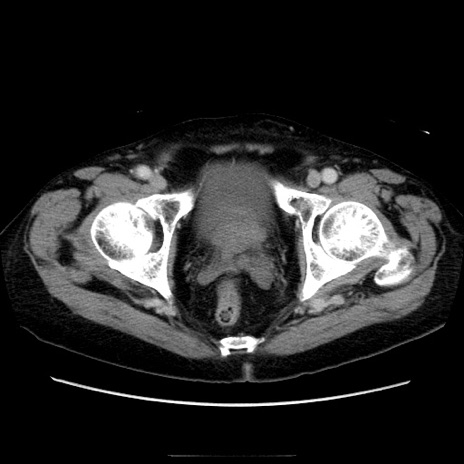

症例21(横断像)

【症例】70歳代男性

【主訴】腹痛

【現病歴】肝硬変・肝細胞癌にてかかりつけの方。約9時間前に食後より腹痛出現。症状が徐々に増悪し、嘔吐出現したため来院。

【既往歴】肝硬変、肝細胞癌(RFA、TACE後)

【身体所見】意識清明、表情苦悶様、BT 36℃、BP 129/78mmHg、P 88bpm、SpO2 97%(RA)、右上腹部から心窩部にかけて圧痛あり、反跳痛なし、筋性防御あり。

【データ】WBC 5800、CRP 0.16